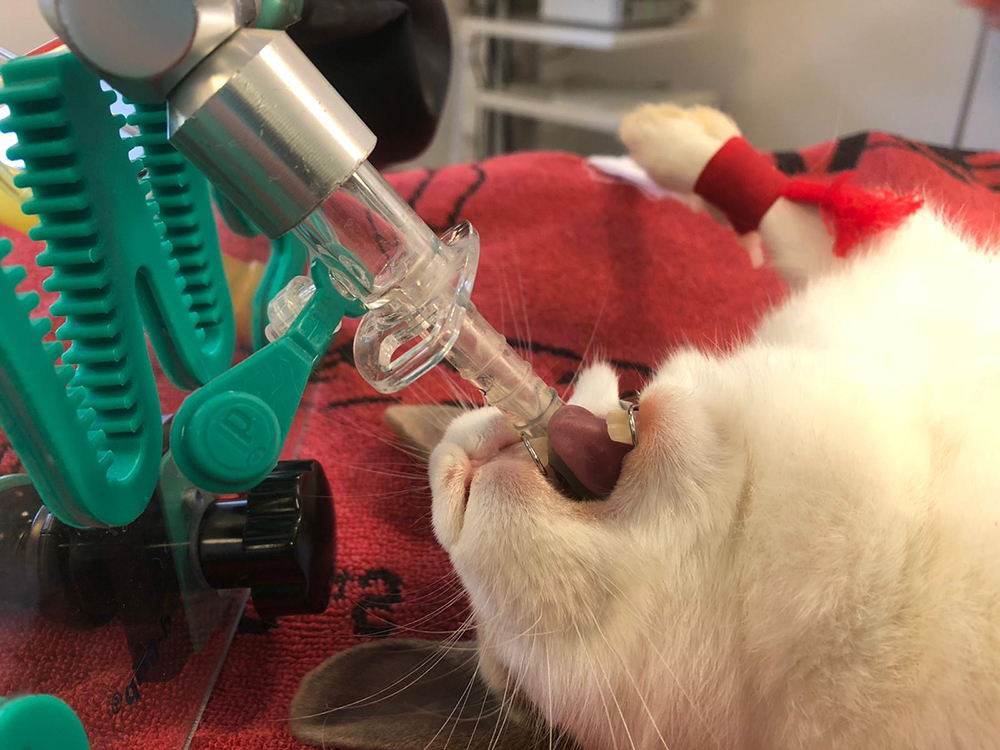

Nadat de voedster de narcose gehad heeft en in slaap is gevallen, wordt ze geschoren in de voorbereidingsruimte. Hierna gaat ze naar de operatiekamer, waar er een buisje (een V-gel, larynxmasker) in de keel wordt ingebracht. Zo kunnen we zuurstof en slaapgas toedienen en tevens de ademhaling monitoren, met behulp van een capnograaf.